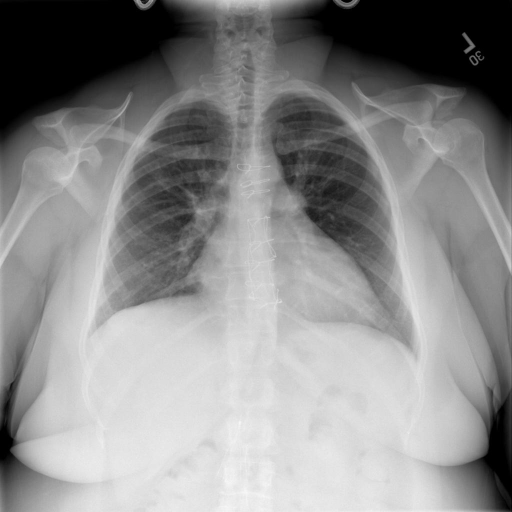

- (1)准备[诊疗报告(中文)](./data/Xray/openi-zh.json)和[X光影像](https://pan.baidu.com/s/13GBsDMKf6xBZBSHpoWH_EA?pwd=k9sh)在`data/Xray`文件夹下; - (2)开始训练: ```bash # 设置CUDA变量,主要是为了解决有时候直接训练而出现无法正确加载到显卡问题 export CUDA_VISIBLE_DEVICES=0,1,2,3 # 开始训练 bash finetune_XrayGLM.sh ``` 这里的复现过程非常简单,主要是很多过程我们都为大家准备好了,大家可以随时复现一个自己的`XrayGLM`。 ### 4.模型训练(通用) - [【官方视频教程】XrayGLM微调实践](https://www.bilibili.com/video/BV1Yh4y147gx/) - [复旦大学《大语言模型理论与实践》](https://intro-llm.github.io/) ## 效果展示 *以下效果来自于**低质量**的数据训练和权重 影像诊断: |X光影像|诊疗报告(医生)|XrayGLM| |:-|:-|:-| |![](./data/Xray/2_1.png)|根据X射线图像,心脏大小正常,肺部看起来很清晰。已经排除了肺炎、积液、水肿、气胸、腺病、结节或肿块的存在。该发现表明一切正常。换句话说,总体印象是胸部正常。|X光片显示,心脏大小正常。肺部没有气胸或胸腔积液的证据。骨骼结构看起来没有任何异常。总的来说,X光片表明没有发现急性心肺疾病的迹象。| |![](./data/Xray/2882_1.png)|X光图片显示没有扭曲的区域、可疑的骨质不透明度或胸腺积液。心脏大小轻微增大,但非常稳定。此外,没有气胸的证据,肺野也正常。总体来说,X光片显示没有急性心脏异常,但要注意轻微的心脏扩大。|X光片显示,心脏大小正常。肺部和纵隔轮廓清晰,没有气胸或胸腔积液的证据。骨骼结构完整,没有任何急性异常。| |![](./data/Xray/2577_1.png)|心影形态在正常范围内。没有急性骨质异常。有可能出现没有明显的吸水或肺实质状况的线索。没有大面积积液或气胸。有可能怀疑其有误吸或肺实质问题。为了确诊和治疗,可能需要进行适当的影像学随访。|心脏大小正常,肺部和纵隔轮廓清晰。没有急性异常或活动受限的证据。没有任何明显的气胸、胸腔积液或肺不张的迹象。此外,也没有发现任何局灶性骨质异常或其他急性疾病。| 多轮对话: |X光影像|诊疗报告(医生)| |:-|:-| |![](./data/Xray/861_1.png)|右侧主动脉突出观察到。心脏大小正常。胸部未发现明显的肺气肿、胸膜积液或可疑的肺部病变。报告指出已知右侧主动脉情况正常。| ```bash >> X光影像路径:./data/Xray/861_1.png >> 用户:这是一张什么图? >> XrayGLM:这张图片显示的是一张肺部检查的X光片。 >> 用户:请描述这张胸部X光片的诊断结果 >> XrayGLM:心脏大小正常,肺部清晰。没有急性心肺疾病的证据。 >> 用户:是否存在肺气肿? >> XrayGLM:没有肺气肿。心脏大小正常,肺部清晰。没有发现急性心肺疾病的证据。 >> 用户:平时饮食该注意什么? >> XrayGLM:饮食应该健康,均衡。建议增加蛋白质的摄入量,因为蛋白质有助于维持肌肉和骨骼的健康。多食用蔬菜、水果、全谷物以及健康的脂肪来源如橄榄油、鱼类等可以帮助获得足够的维生素和矿物质。此外,避免过度饮酒或吸烟,这些习惯可能会对心脏健康产生负面影响。 ``` ## 未来展望 1. 模型的能力更多来源于数据的支持,`OpenI-zh`作为微调数据集,其数据量足以支持研究,在更广泛的任务和性能表现上,我们认为**在大规模数据集上预训练并在高质量少量数据集上微调是一种可行的方案**; 2. 普遍意义的理解上,视觉多模态模型=视觉模型+语言模型。除了需要关注视觉模型信息与语言模型输出的搭配外,还需要**额外关注到语言模型的加强,在人机的对话中,尤其是医疗语言模型的问答上,除了专业的医疗问题回答,带有人文情怀的有温度的回答更应该是我们追寻的目标**。 3. **高精度的模型永远打不过大参数的模型**,如果在6B模型和13B模型上选择微调,请在资源充足情况下选择13B的大参数模型; ## 项目致谢 1. [VisualGLM-6B](https://github.com/THUDM/VisualGLM-6B)为我们提供了基础的代码参考和实现; 2. [MiniGPT-4](https://github.com/Vision-CAIR/MiniGPT-4)为我们这个项目提供了研发思路; 3. ChatGPT生成了高质量的中文版X光检查报告以支持XrayGLM训练; 4. [gpt_academic](https://github.com/binary-husky/gpt_academic)为文档翻译提供了多线程加速; 5. [MedCLIP](https://github.com/RyanWangZf/MedCLIP) 、[BLIP2](https://huggingface.co/docs/transformers/main/model_doc/blip-2) 、[XrayGPT](https://github.com/mbzuai-oryx/XrayGPT) 等工作也有重大的参考意义; ![](./assets/images/mpu.png) 这项工作由[澳门理工大学应用科学学院](https://www.mpu.edu.mo/esca/zh/index.php)硕士生[王荣胜](https://github.com/WangRongsheng) 、[段耀菲](https://github.com/IsBaSO4) 、[李俊蓉](https://github.com/lijunrong0815)完成,指导老师为檀韬副教授、[彭祥佑](http://www.patrickpang.net/)老师。 *特别鸣谢:[USTC-PhD Yongle Luo](https://github.com/kaixindelele) 提供了有3000美金的OpenAI账号,帮助我们完成大量的X光报告翻译工作 ## 免责声明 本项目相关资源仅供学术研究之用,严禁用于商业用途。使用涉及第三方代码的部分时,请严格遵循相应的开源协议。模型生成的内容受模型计算、随机性和量化精度损失等因素影响,本项目无法对其准确性作出保证。即使本项目模型输出符合医学事实,也不能被用作实际医学诊断的依据。对于模型输出的任何内容,本项目不承担任何法律责任,亦不对因使用相关资源和输出结果而可能产生的任何损失承担责任。 ## 项目引用 如果你使用了本项目的模型,数据或者代码,请声明引用: ```bash @misc{wang2023XrayGLM, title={XrayGLM: The first Chinese Medical Multimodal Model that Chest Radiographs Summarization}, author={Rongsheng Wang, Yaofei Duan, Junrong Li, Patrick Pang and Tao Tan}, year={2023}, publisher = {GitHub}, journal = {GitHub repository}, howpublished = {\url{https://github.com/WangRongsheng/XrayGLM}}, } ``` ## 使用许可 此存储库遵循[CC BY-NC-SA](https://creativecommons.org/licenses/by-nc-sa/4.0/) ,请参阅许可条款。